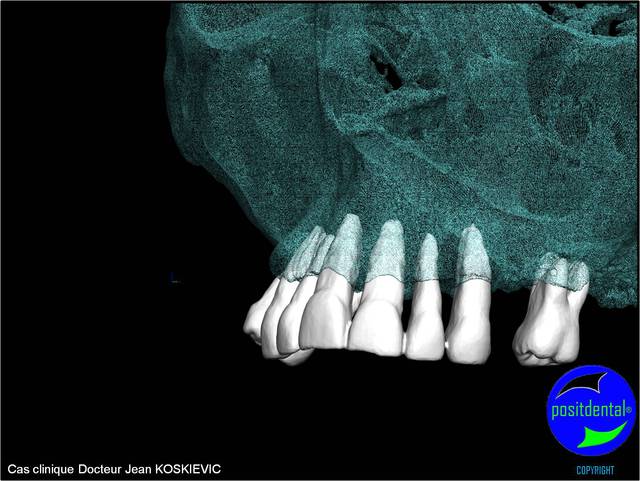

Cookie Consent byPrivacyPolicies.comExtractions MCI en 1 chirurgie - Eugenol

Wax up 3d positdental 6 gjokn0 - Eugenol

Wax up 3d positdental 7 w35rkr - Eugenol